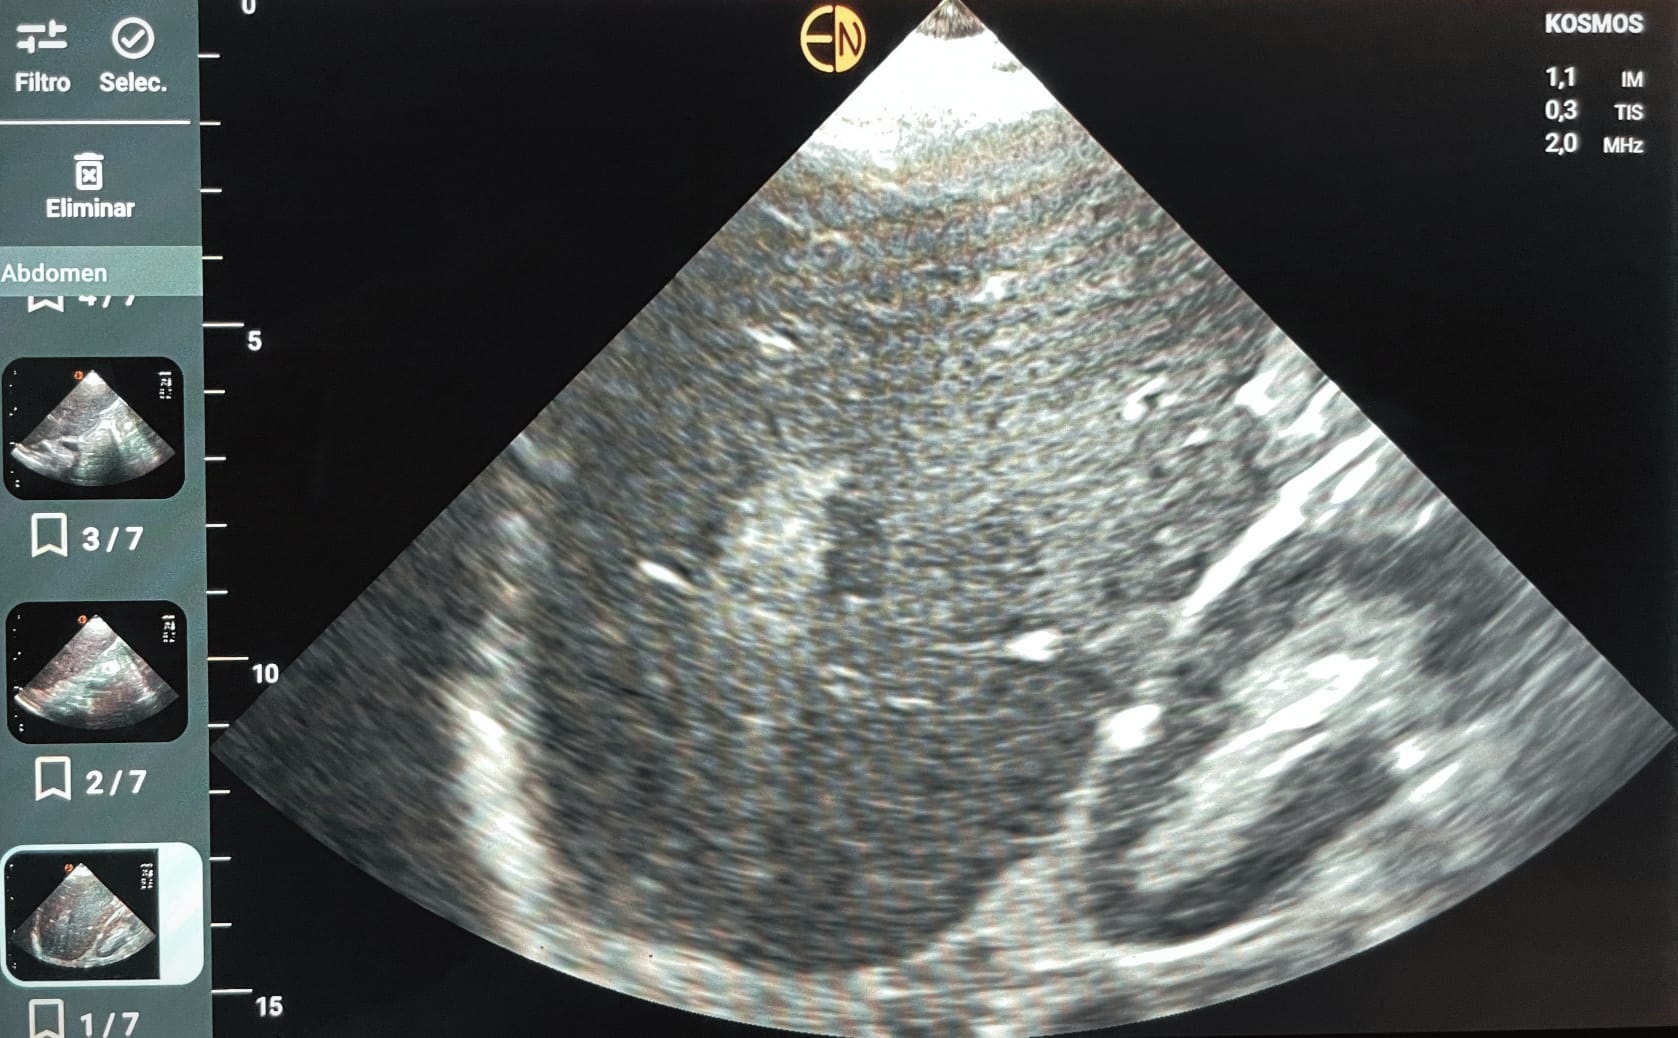

Ecografía POCUS abdomen: se identifican al menos dos imágenes hiperecogénicas en parenquima hepático, con regiones de aspecto algo heterogéneo, la mayor de ellas de 4,9 cm diámetro máx. No líquido libre. Vesícula distendida, sin signos de colecistitis o dilat vía biliar.